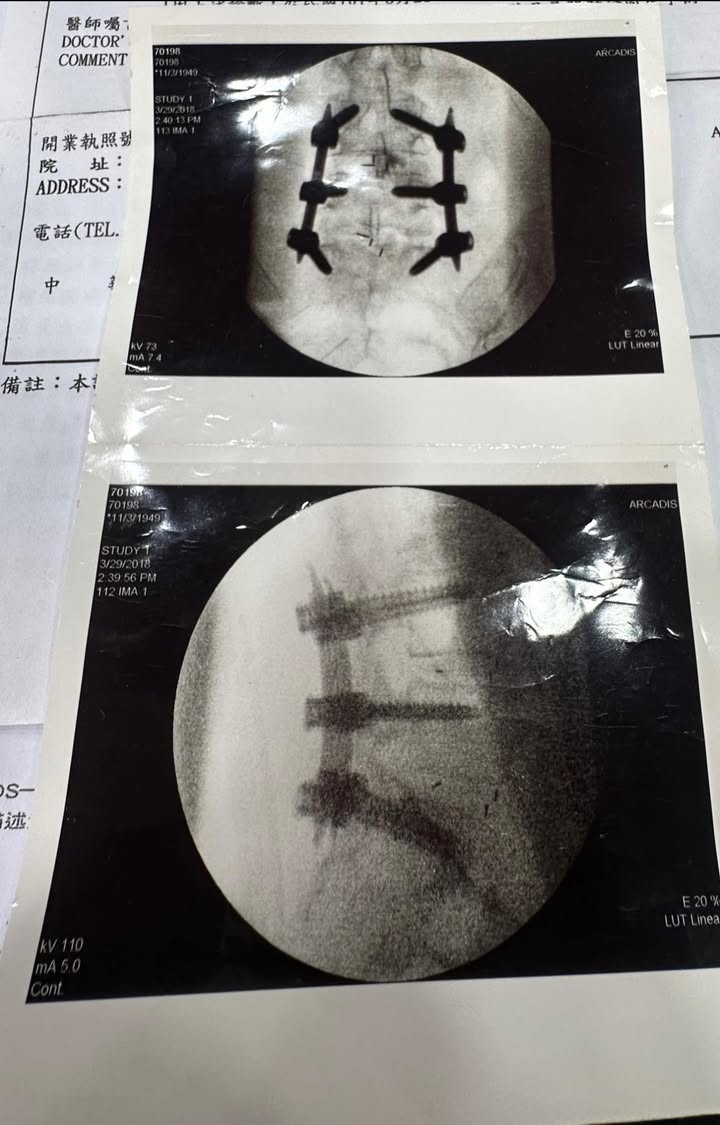

Cervical Spine Treatment Cases 精彩回顧 2024.09.06 2024.09.09 做完腰椎融合手術打了六支釘子之後嚴重惡化 2024.09.11 椎弓解離骨折導致滑脫一定要開刀嗎 2024.09.15 脊椎手術後嚴重沾黏案例 2024.09.18 又是脊椎手術後遺症沾黏 2024.09.20 脊客救援俠醫出任務 2024.09.21 2024.09.21 2024.09.24 2024.09.26 2024.09.26 2024.09.29 2024.10.02 颱風天必須提到這首歌六年級五年級才懂 2024.10.03 2024.10.04 ← 上一頁 22 23 24 25 26 下一頁 →